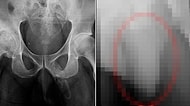

Diz Kapağındaki Ağrıdan Ötürü Gittiği Hastanede Çekilen Röntgenle Penisinde Kemikleşme Olduğunu Öğrenen Adam İnsan vücudu o kadar karmaşık bir yapıdır ki; ba... 26 Ağustos 2019